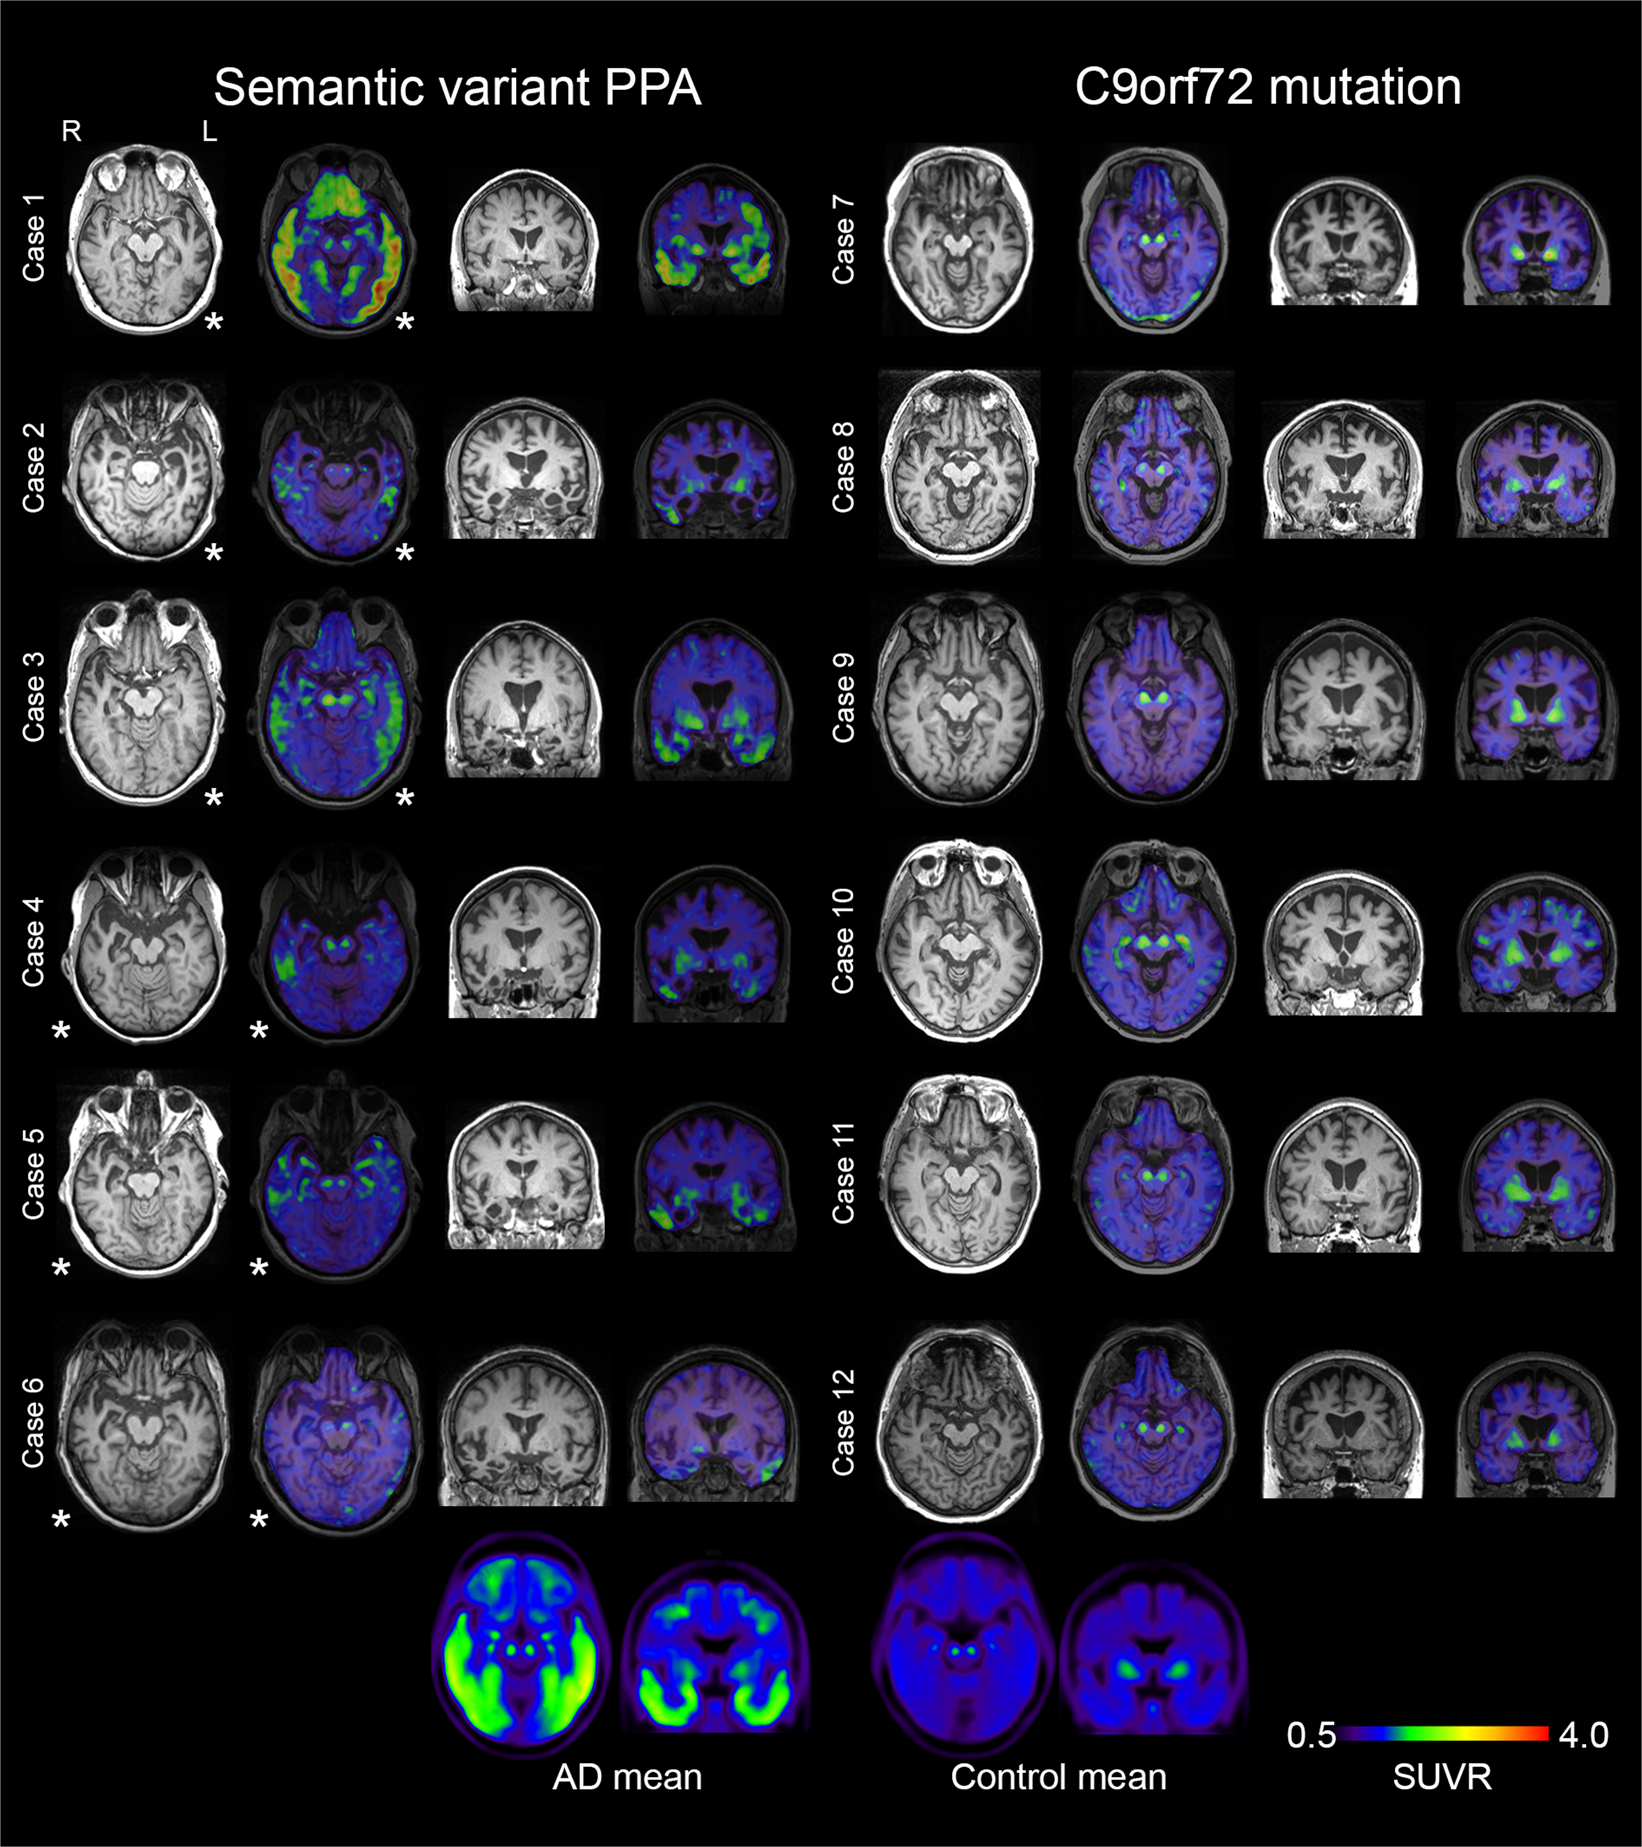

MRI and 18F-Flortaucipir PET scans in svPPA and C9orf72-mutation carriers. Transversal and coronal slices of structural (T1-mprage) MRI scans and 18F-Flortaucipir PET scans are shown for all included subjects with semantic variant primary progressive aphasia (svPPA) and bvFTD due to a hexanucleotide expansion in the C9orf72-gene. Case numbers correspond to case numbers in Table 1. Below the individual images are mean SUVR-images of 40 AD patients and the 54 controls in MNI-space, included for comparative purposes. The images are presented in radiological orientation (left in the image corresponds to patient right). Asterisks indicate the most affected side in the svPPA cases. Scale bar for PET-scans represents standardized uptake value ratios (SUVR). An identical figure with SUVR range 0.5–3 is included as Supplementary Fig. 5.